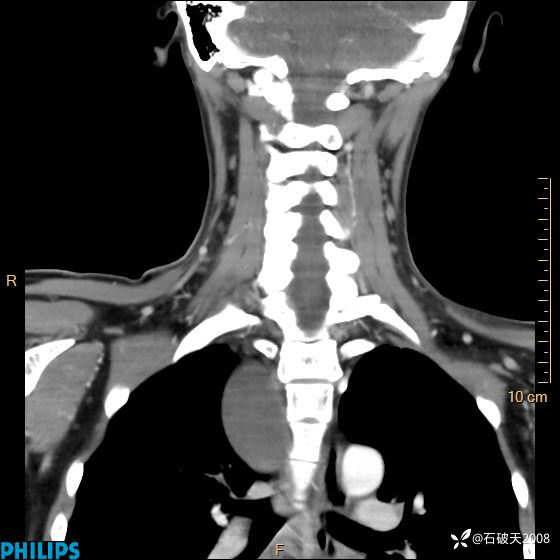

冠状位

静脉期